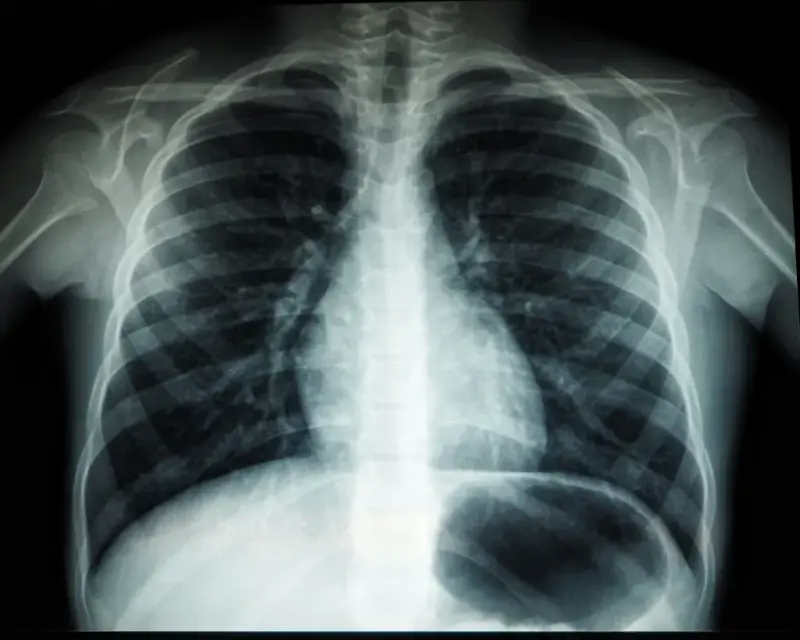

Badania obrazowe stanowią podstawę w diagnostyce wielu schorzeń. Podstawową przeszkodą w ich przeprowadzeniu jest brak wykwalifikowanego personelu, który szczegółowo opisze wyniki. Z pomocą przychodzi teleradiologia, która może znacząco usprawnić całą procedurę diagnostyczną. Czym dokładnie jest i na jakich zasadach funkcjonuje?

Teleradiologia to usługa polegająca na zdalnym opisie badań obrazowych – tomografii komputerowej oraz rezonansu magnetycznego. Mogą być one wykonane w dowolnym miejscu – przychodni, szpitalu czy ośrodku zdrowia, a następnie są przekazywane w formie zapisu komputerowego do firmy specjalizującej się w teleradiologii. Metoda ta pozwala znacząco ograniczyć czas potrzebny na wykonanie opisu, a tym samym przyspieszyć całą procedurę diagnostyczną. Więcej na jej temat można dowiedzieć się na stronie https://telediag.pl/. Jest to witryna firmy, która świadczy usługi teleradiologiczne dla jednostek z całego kraju.

Teleradiologia zyskała popularność w czasach, gdy coraz więcej pacjentów korzysta z porad lekarskich online. Opis badań obrazowych na odległość również nie stanowi żadnego problemu, a wręcz przeciwnie – może rozwiązać wiele problemów, z którymi borykają się szpitale i przychodnie. W wielu miejscach w ogóle nie ma możliwości wykonania badań obrazowych, jednak problemem nie jest brak sprzętu, a lekarza, który opisałby wyniki. Niestety, tomografia komputerowa czy rezonans magnetyczny, pomimo dużej wartości diagnostycznej, nie są przydatne lekarzowi specjaliście, jeśli nie posiadają stosownego opisu. Sporządzenie go leży w kompetencji radiologa, który może świadczyć usługi zdalnie. Teleradiologia pozwala zoptymalizować koszty działalności podmiotów leczniczych i do minimum skrócić czas oczekiwania na wyniki. Jest to korzystne zarówno dla pacjenta, jak i dla lekarza prowadzącego diagnostykę. Wyniki opisywane są w trybie planowym – jednostka zlecająca otrzymuje je w ciągu 5 dni, podczas gdy wynik opisywany tradycyjną metodą często dostępny jest dopiero po 2 tygodniach. Teleradiologia bazuje na systemach komputerowych, które są zabezpieczone w odpowiedni sposób. Nie trzeba więc obawiać się wycieku danych czy jakichkolwiek awarii, które mogłyby zakłócić pracę. Z tej usługi korzysta już wiele ośrodków medycznych, zwłaszcza z mniejszych miejscowości. Niemniej jednak jest ona stosunkowo nowa na rynku, dlatego w przyszłości prawdopodobnie większość przychodni i szpitali przejdzie na tryb zdalny opisu badań radiologicznych, mając na uwadze wynikające z niego korzyści.